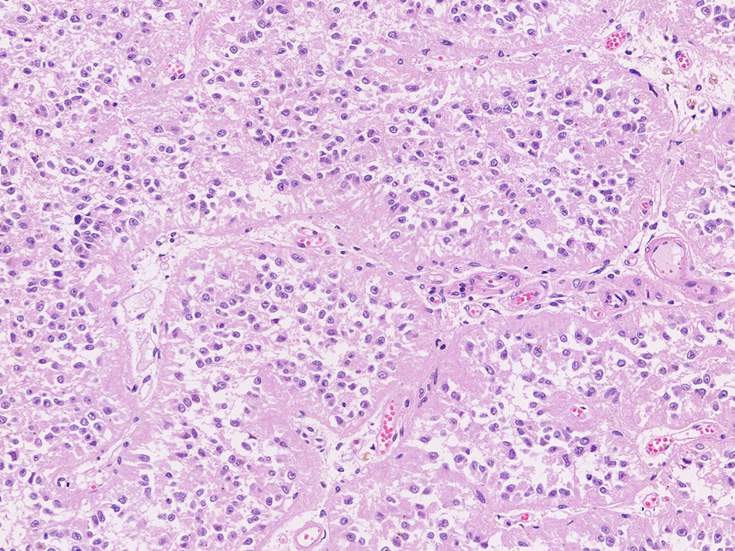

松果体の腫瘍 pinealoma

松果体には松果体の細胞またはその前駆細胞から発生する腫瘍の他に多くの腫瘍, glioma, meningiomaあるいは, 胚細胞腫germ cell tumorが発生する。

Pineal cell tumor 松果体細胞またはその前駆細胞より発生する。